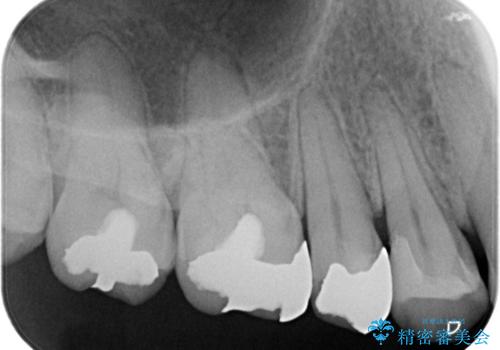

銀歯がとれた!セラミックインレーによる修復

- 銀歯が取れたことを主訴に来院されました。

虫歯も認め、虫歯を除去したのちセラミックインレーにて修復しております。

適合のよい修復を行うことで、再び虫歯になることを予防します。